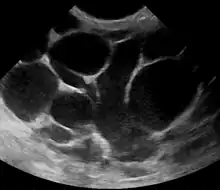

However, if the doctor is not sure whether the mass is an abscess or a tumor, a breast ultrasound may be performed. The ultrasound provides a clear image of the breast tissue and may be helpful in distinguishing between simple mastitis and abscess or in diagnosing an abscess deep in the breast. The test consists of placing an ultrasound probe over the breast.

Breast abscess

An abscess (or suspected abscess) in the breast may be treated by ultrasound-guided fine-needle aspiration (percutaneous aspiration) or by surgical incision and drainage; each of these approaches is performed under antibiotic coverage. In case of puerperal breast abscess, breastfeeding from the affected breast should be continued where possible.[23][40]

For small breast abscesses, ultrasound-guided fine needle aspiration such as to completely drain the abscess is widely recognized as a preferred initial management.[41]

One recommended treatment includes antibiotics, ultrasound evaluation and, if fluid is present, ultrasound-guided fine needle aspiration of the abscess with an 18 gauge needle, under saline lavage until clear.[42] The exudate is then sent for microbiological analysis for identification of the pathogen and determination of its antibiotic sensitivity profile,[43] which may in turn give an indication for changing the antibiotics. At follow-up, a mammography is performed if the condition has resolved; otherwise the ultrasound-guided fine-needle aspiration with lavage and microbiological analysis is repeated.[44] If three to five aspirations still do not resolve the condition, percutaneous drainage in combination with placement of an indwelling catheter is indicated, and only if several attempts at ultrasound-guided drainage fail, surgical resection of the inflamed lactiferous ducts (preferably performed after the acute episode is over).[45] It is noted, however, that even the excision of the affected ducts does not necessarily prevent recurrence.[45]